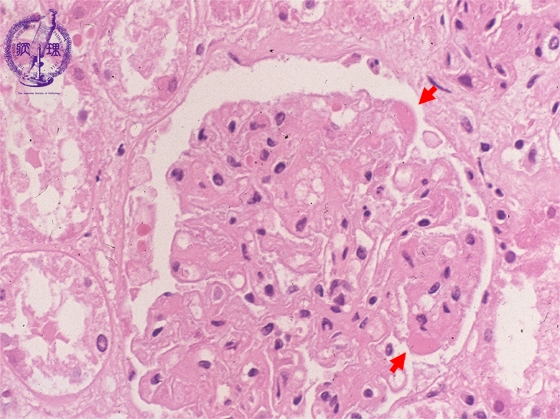

Microscopic findings (HE, high power view): Note the hemispheric shaped eosinophilic glomerular deposits (red arrows).

Click the image to see the enlarged image.